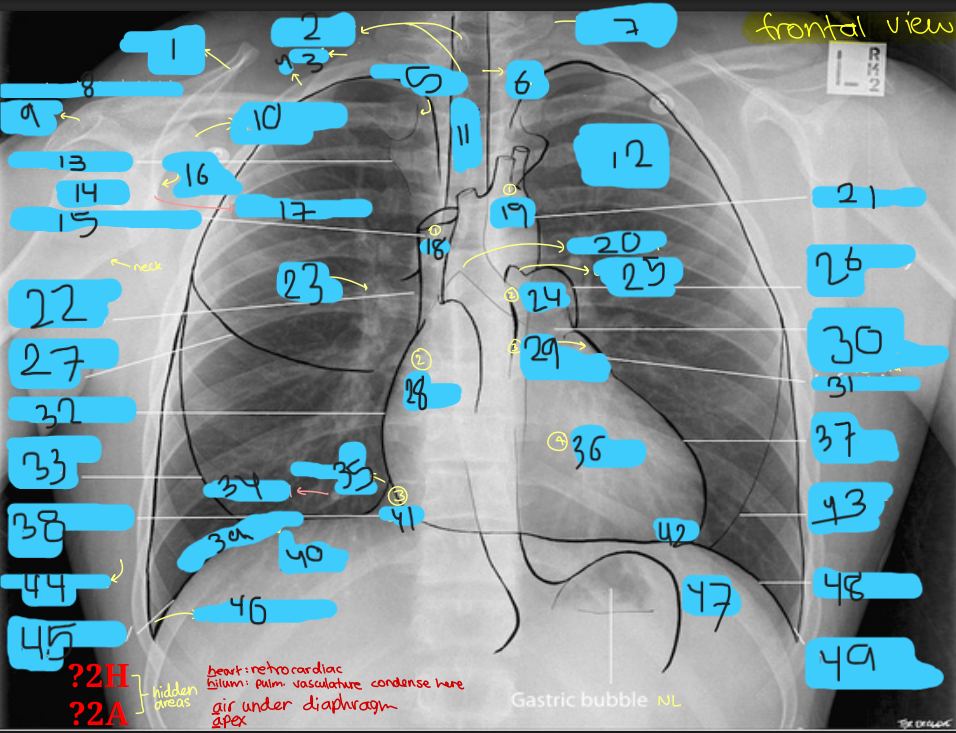

Heart right border

Right atrium

Superior vena cava entering superiorly

Inferior vena cava often seen at its lower margin

Heart left border

Left ventricle and left atrial appendage

The pulmonary artery

Aortopulmonary window

Aortic notch extend superiorly.